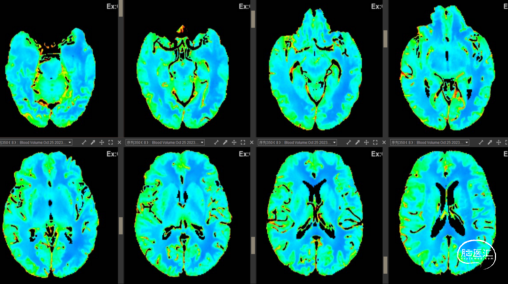

2023-10-25 我院急诊头颅CTP:右侧大脑中动脉供血区MTT、Tmax均延长,呈低灌注表现。

2023-10-25 术前CBF示右侧大脑中动脉供血区血流量减少。

2023-10-30 术后CBF示右侧大脑中动脉供血区血流量恢复正常。